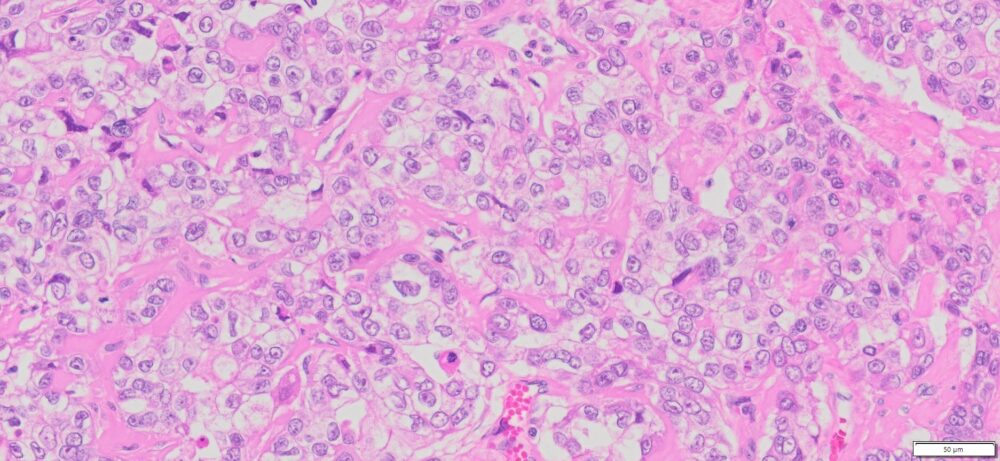

Description

| Organ& Tissue | Pathology Diagnosis | Gender/Age | % Tumor Area | Grade | TMN Stage | IHC Biomarkers |

| Human Ovary | Ovarian clear-cell carcinoma or ovarian clear-cell adenocarcinoma | Female/67 | 80% | II | pT1aNxMx | ER(-),PR(-),Pax8 (+),WT1(-),p53(-),Ki67(70%) |

Human tissue was fixed in formalin immediately after excision and embedded in paraffin. The tissue sections were 5 µm in thickness and mounted each on positively charged glass slides.